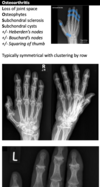

**Psoriatic arthropathy** Pencil in cup X-ray showing some of changes in seen in psoriatic arthropathy. Note that the DIPs are predominately affected, rather than the MCPs and PIPs as would be seen with rheumatoid. Extensive juxta-articular periostitis is seen in the DIPs but the changes have not yet progressed to the classic 'pencil-in-cup' changes that are often seen.

Psoriatic arthritis

Arthritis hands: compare osteoarthritis, rheumatoid arthritis and psoriatic arthritis